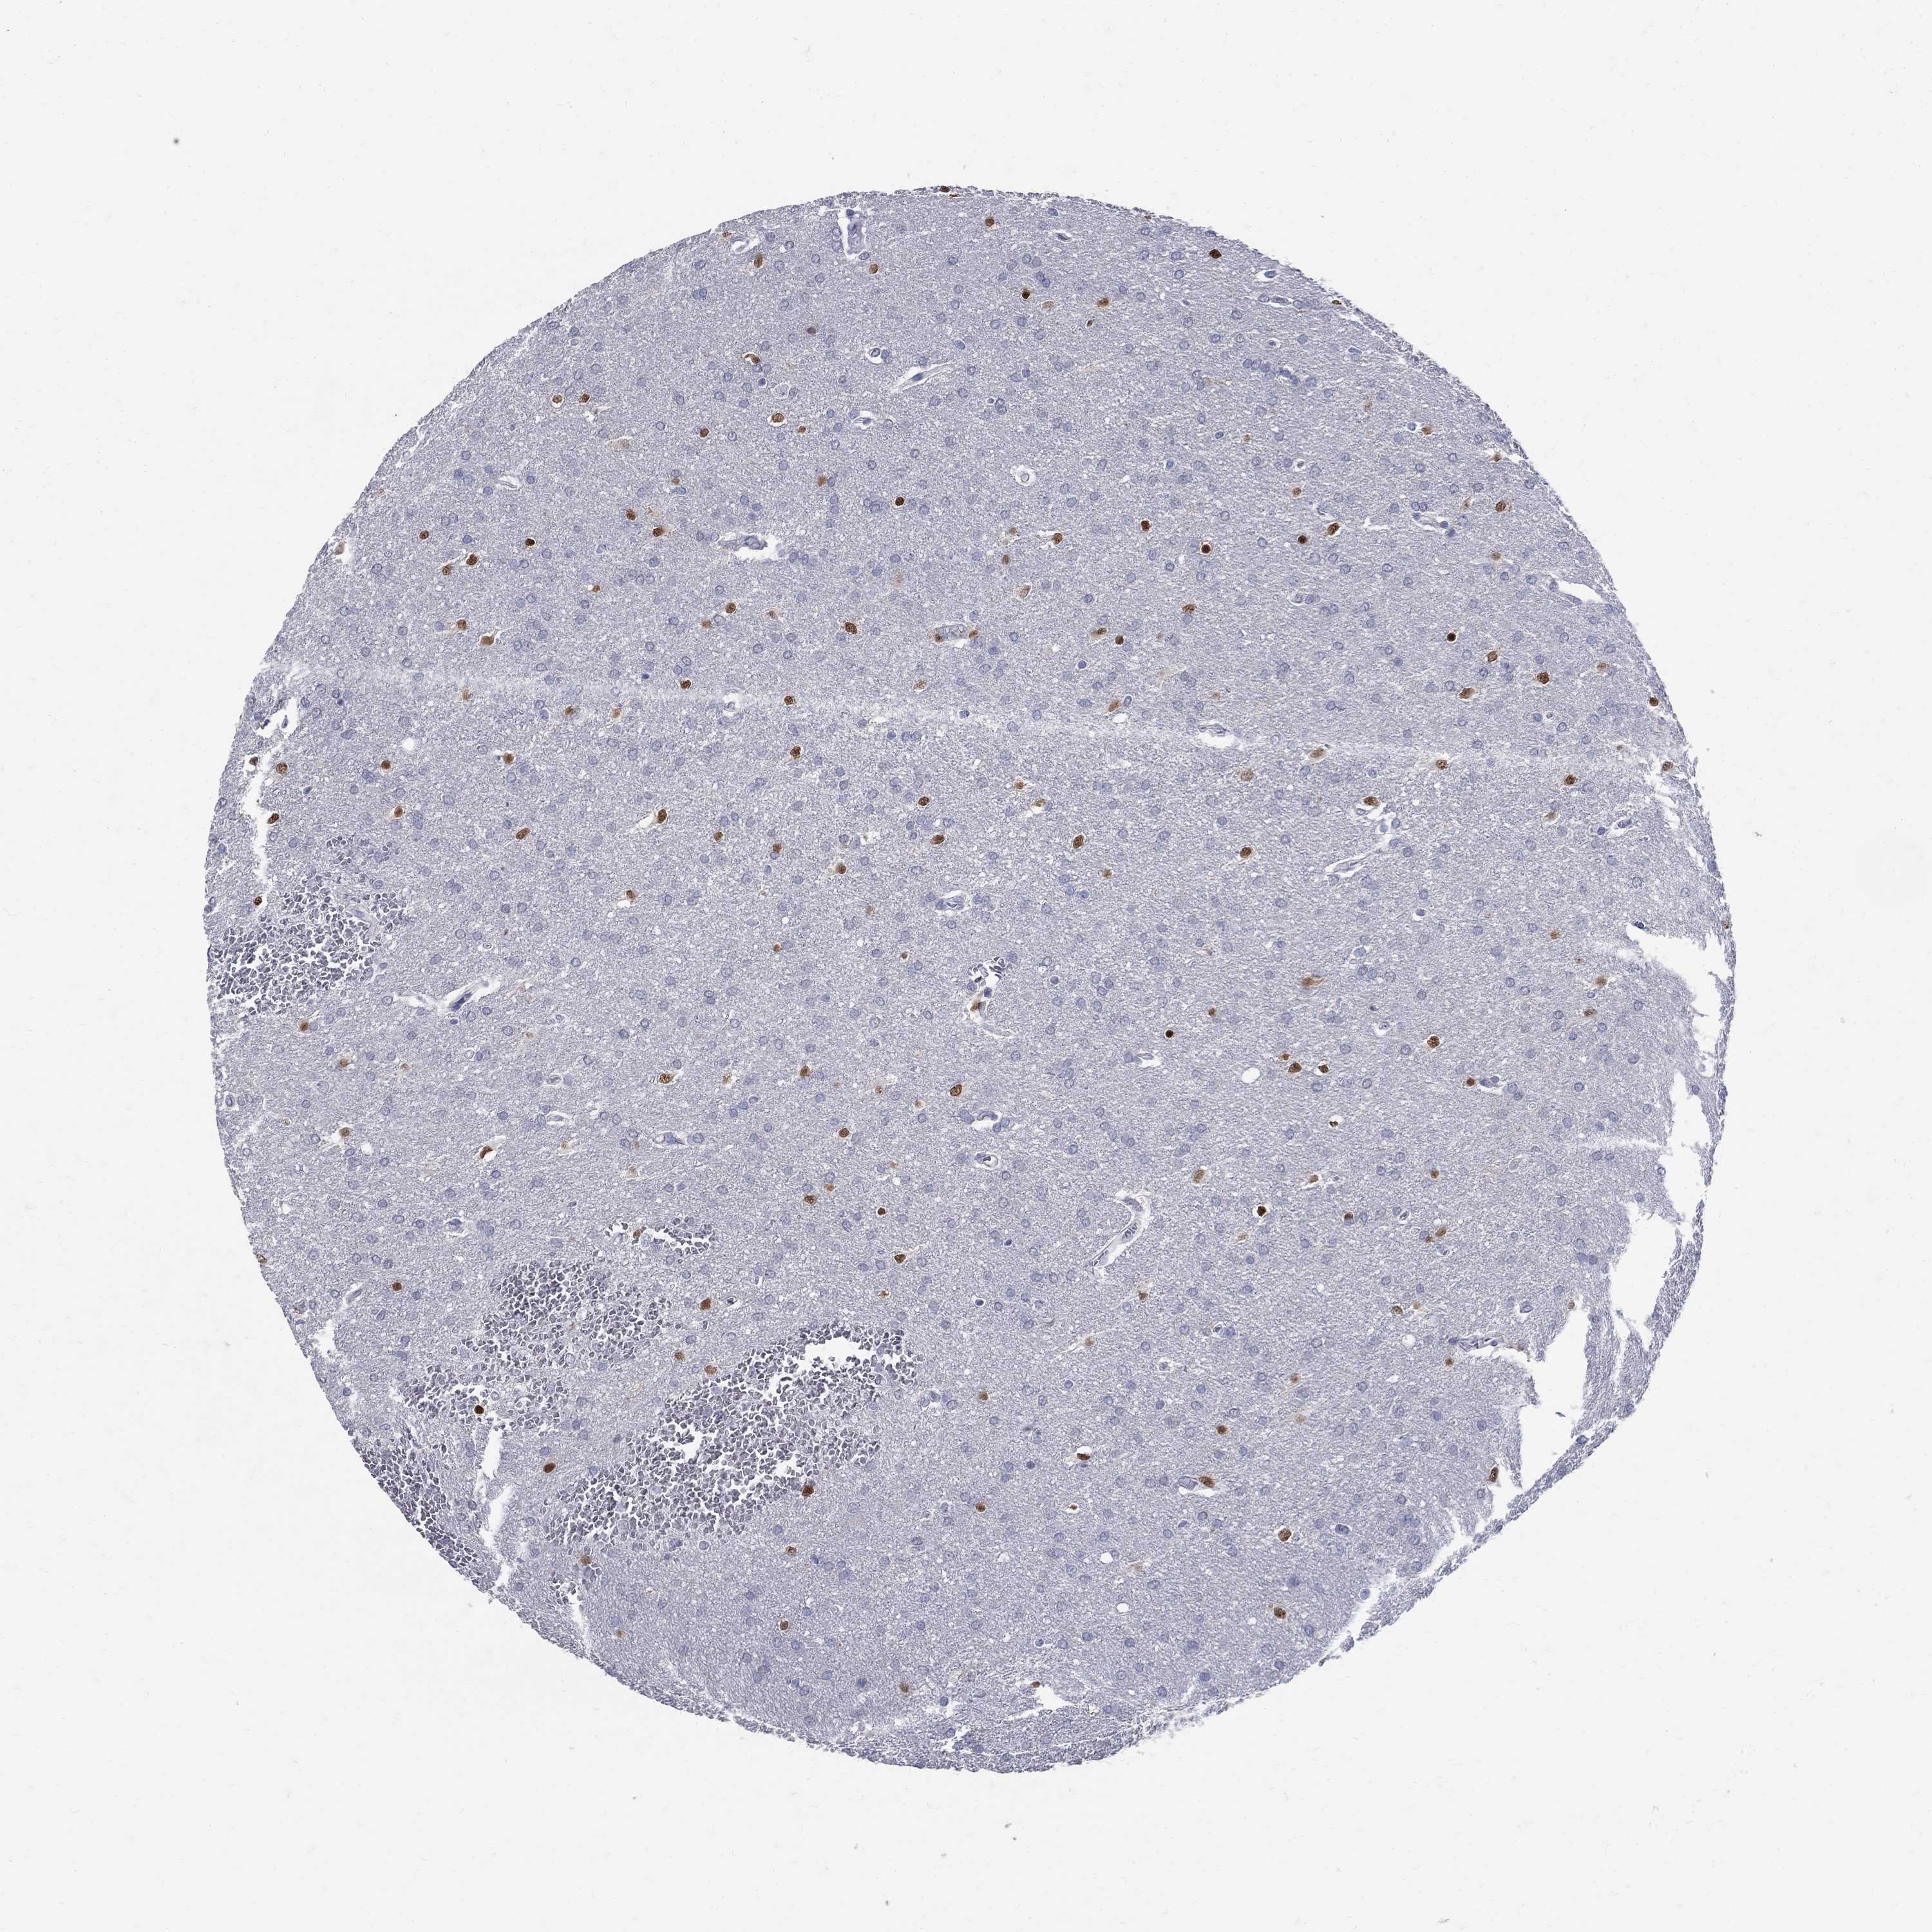

GLIOMA - Protein expressioni

A mouse-over function shows sample information and annotation data. Click on an image to view it in a full screen mode. Samples can be filtered based on level of antibody staining by selecting one or several of the following categories: high, medium, low and not detected. The assay and annotation is described here.

Note that samples used for immunohistochemistry by the Human Protein Atlas do not correspond to samples in the TCGA dataset.

Antibody stainingi

Antibody staining in the annotated cell types in the current human tissue is reported as not detected, low, medium, or high, based on conventional immunohistochemistry profiling in selected tissues. This score is based on the combination of the staining intensity and fraction of stained cells.

Each image is clickable and will lead to virtual microscopy that enables deeper exploration of all samples and also displays staining intensity scores, fraction scores and subcellular localization as well as patient and tissue information for each sample.

Antibody HPA045725

Antibody CAB079745

Staining

High

Medium

Low

Not detected

Intensity

Strong

Moderate

Weak

Negative

Quantity

>75%

75%-25%

<25%

None

Location

Nuclear

Cytoplasmic/membranous

Cytoplasmic/membranous,nuclear

Glioma, malignant, Low grade

Glioma, malignant, High grade